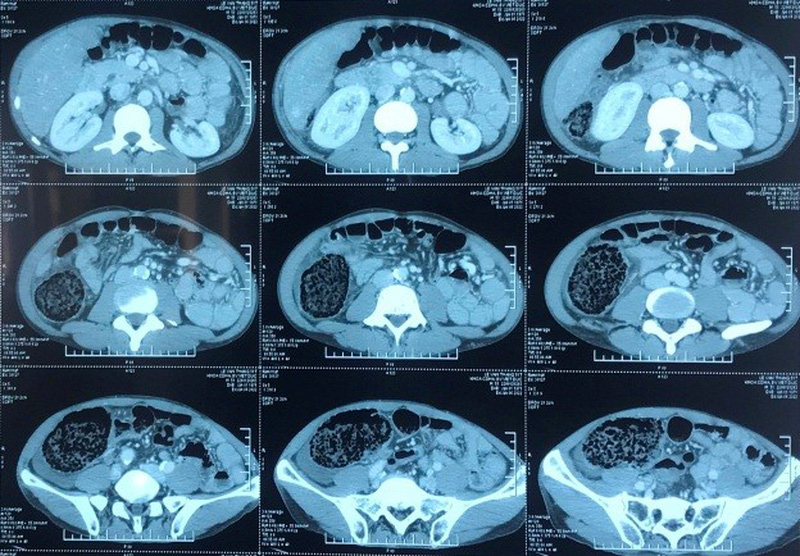

Các bác sĩ thăm khám thấy người bệnh có những triệu chứng điển hình của tắc ruột. Chẩn đoán hình ảnh trên phim chụp cắt lớp vi tính ổ bụng có tiêm thuốc cản quang chụp có hình ảnh tắc ruột giãn, ứ đọng phân trong đại tràng lên theo dõi do u đại tràng góc gan, xơ gan tăng áp lực tĩnh mạch cửa, dịch tự do ổ bụng.

TS.BS Nguyễn Xuân Hòa, Khoa Phẫu thuật Tiêu hóa cho biết: Kiểm tra trong mổ phát hiện gan xơ đầu đinh cả hai thùy, đặc biệt manh tràng, đại tràng giãn lớn, đường kính khoảng 10cm, gây rách thanh cơ trên đoạn dài 15x4cm, chỉ còn lớp niêm mạc, có lấm chấm hoại tử trên bề mặt, kiểm tra toàn bộ khung đại tràng, trực tràng mềm mại, không thấy u cục. Người bệnh được chẩn đoán: Tắc đại tràng theo dõi do hội chứng Ogilvie, được phẫu thuật cắt đoạn manh tràng, đại tràng lên do rách thanh cơ, hoại tử đại tràng, nối hồi tràng với đại tràng lập lại lưu thông tiêu hóa.

Triệu chứng lâm sàng giống như một bệnh nhân bị tắc ruột: đau bụng cơn, nôn, bụng chướng, bí trung đại tiện, nếu có các biến chứng như vỡ, thủng đại tràng thì có thêm các triệu chứng như sốt, viêm phúc mạc. Hội chứng Ogilvie hầu như không thể phân biệt được với tắc nghẽn cơ học nếu chỉ dựa trên các dấu hiệu và triệu chứng lâm sàng. Cắt lớp vi tính là công cụ hữu ích trong việc chẩn đoán và phân biệt bệnh.